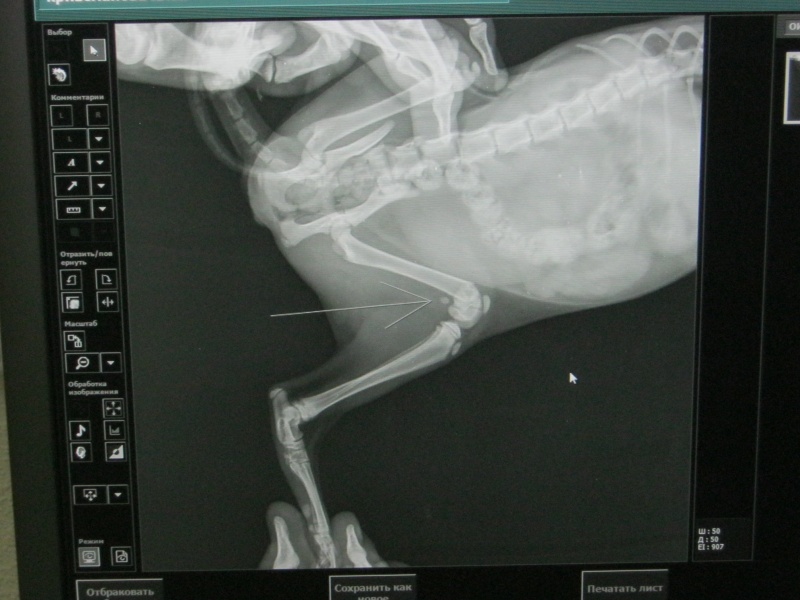

Снова беда, снова человеческая жестокость!! Очевидцы утвержают, что кроху выбросили из окна специально, потому что с такой траекторией полета она не могла сама выпасть из окна. Котенок приземлился на проезжую часть и некоторое время просто не подавал признаков жизни. У малышки сломано бедро, вероятно есть ушибы внутренних органов, скорее всего сотрясение, разбита мордочка. Сегодня мы отвезли малышку в клинику "Ветлекарь". Сутки за котенком будут наблюдать, посмотрят на ее состояние, сделают УЗИ при необходимости, тк вчера она сходила в туалет с кровью. И если состояние Хлои будет стабильно нормальным, то завтра же проведут остеосинтез. Цена операции 8000. Что понадобится еще, пока не известно. Прошу помощи в сборе денег на операцию для малышки. Если все будет хорошо, то забирать Хлою будем уже в воскресенье. У нас еще на доведен до ума Рыжик с подобной травмой и вот еще одна бедолага((( Помогите, пожалуйста!!

Операцию Хлое сделали сегодня днем. Сейчас малышка полностью вышла из наркоза, но на лапку пока не опирается. Ушиба легких врачи не обнаружили, дыхание у Хлои ровное. Завтра утром будет точная информация по ее состоянию. Врачи еще наблюдают за ней. Лапка будет восстанавливаться больше месяца. И потом еще одна операция по удалению спиц. Если все хорошо, то забирать кошечку будем завтра.

Два дня назад Хлою возили на снятие швов. У котенка все хорошо, она достаточно активна и вполне здорова, если бы не титановые спицы в лапке. Через месяц снова рентген и будем решать, удалять или оставлять спицы. Это снова операция, снова вскрывать коленный сустав, но и оставлять как? Котенку же расти(( У кого нибудь был такой опыт?

С высокой вероятностью всё будет хорошо, это методика называется "метод перекрещенных спиц". Довольно успешно применяется при т.н. эпифизиолизе, т.е. переломе по зоне роста у молодых животных (котят и щенков).

Бедренная кость будет абсолютно такой же длины как и вторая, по мере роста кости в длину, кость будет как бы "соскальзывать со спиц" или "сниматься с шомпола". Снятие (извлечение) спиц не требуется в последствие.

Крайне редко в далекой перспективе возможна миграция спиц, в таком случае в зависимости от показаний - возможно удаление имплантов (спиц).

Сегодня Хлоя была на плановом приеме в клинике "Ветлекарь".

После остеосинтеза прошло больше месяца. Врачи сказали, что процесс заживления идет хорошо, но спицы останутся в лапке. Хлоя уже давно решила сама, что с лапкой у нее все в порядке)) Носится, прыгает, озорничает.